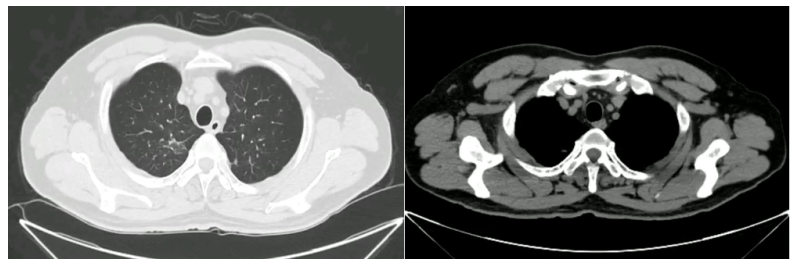

• 门诊胸部CT(2023年10月19日):右上肺尖段可见不规则肿块影(图1)

图1  患者胸部CT2023年10月19日

• 入院第2天(2023年10月20日)胸部增强CT如图2所示,右肺上叶尖段病灶内可见少量强化。

2   患者胸部增强CT2023年10月20